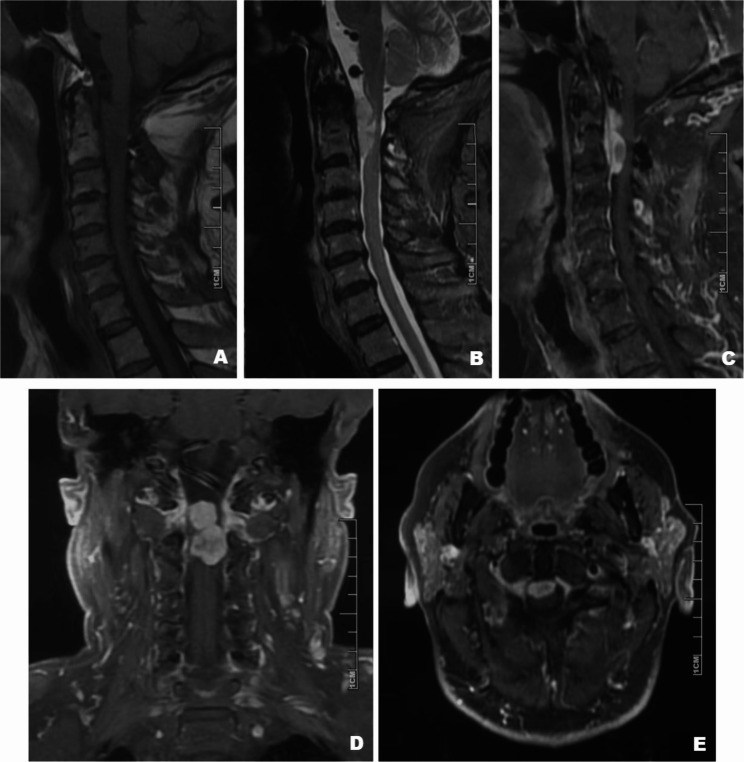

脊索样脑膜瘤(CM)是一种少见的脑膜瘤的组织学变异,通常在颅内发现。椎管内的发生,特别是在颈椎区域,是非常罕见的。我们报告一个独特的情况下,73岁的男性颈椎CM谁经历了肿瘤复发两年后的总切除(GTR)。组织病理学分析证实复发为端粒酶逆转录酶(TERT)启动子C250T突变的间变性脑膜瘤,CNS WHO分级3-标志着该突变与脊柱CM的首次文献关联。该病例强调了脊柱CM的诊断、分子和预后复杂性,并强调了TERT启动子突变在肿瘤行为和分类中的关键作用。

Chordoid meningioma (CM) is an uncommon histological variant of meningioma, typically found intracranially. Intraspinal occurrences, particularly in the cervical region, are exceedingly rare. We report a unique case of a 73-year-old male with cervical spinal CM who experienced tumor recurrence two years after gross total resection (GTR). Histopathological analysis confirmed the recurrence as anaplastic meningioma with telomerase reverse transcriptase (TERT) promoter C250T mutation, CNS WHO Grade 3-marking the first documented association of this mutation with spinal CM. This case underscores the diagnostic, molecular, and prognostic complexities of spinal CM and highlights the critical role of TERT promoter mutation in tumor behavior and classification.